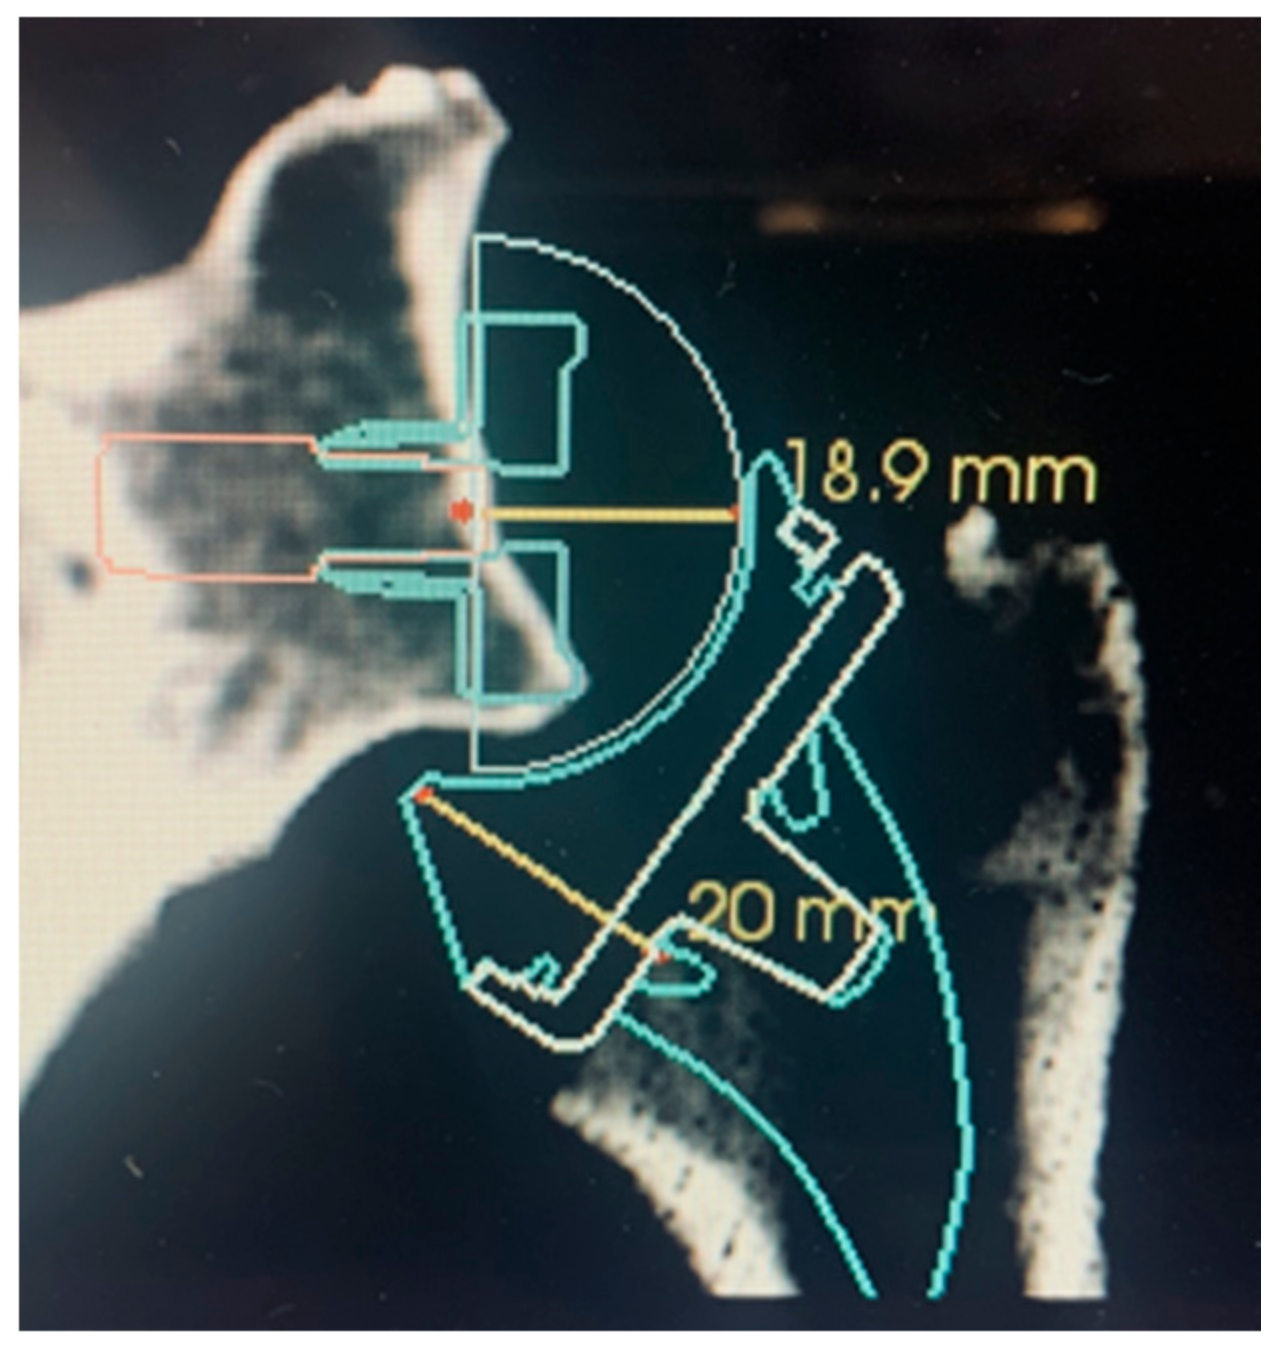

5. Author’s Suggested Technique

- (1)

- The computed sphere that best fits the 3D model of the glenoid concavity is displayed with the glenoid best fit sphere radius (GBFSR), a marker of the glenohumeral size (observed range: 25–45 mm). Patients with GBFS of less than 30 mm are at higher risk of overstuffing.

- (2)

- Lateralization (variation 0 to +10 mm): The surgeon should be cautious with lateralization beyond +5–10 mm depending on the amount of loss of medial bone stock. Excessive superior migration (vertically decentered) but, more importantly, posterior (e.g., B2 glenoid) and anterior subluxation are signs that there will be increased tension when attempting to reduce the RSA.

- (3)

- Distalization (variation: 20 to +40 mm) depends on the amount of cranial humeral head migration. The surgeon should be cautious with distalization beyond 35–40 mm.

5.1. Glenoid Side

5.2. Gap Space Assessment

5.3. Humeral Side